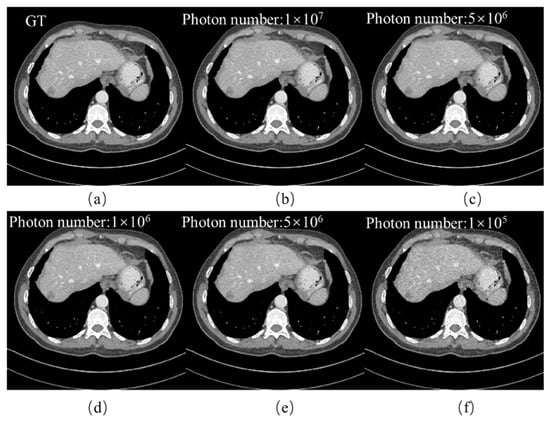

4.3. Noise Robustness Analysis

| Photon Number | 1 × 105 | 5 × 105 | 1 × 106 | 5 × 106 | 1 × 107 |

|---|---|---|---|---|---|

| RMSE | 0.011 | 0.008 | 0.008 | 0.008 | 0.008 |

| PSNR | 39.868 | 41.395 | 41.701 | 42.062 | 42.262 |

| SSIM | 0.979 | 0.986 | 0.987 | 0.987 | 0.988 |